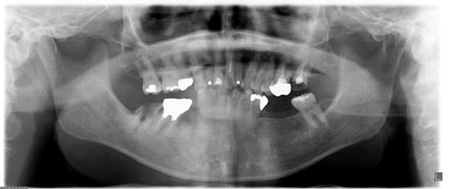

40代男性。右上と左下の歯が喪失して、そのままになっている。

左上と右下の歯は治療途中で崩壊しており、このまま治療中断を繰り返せば歯を喪失することが予想される。